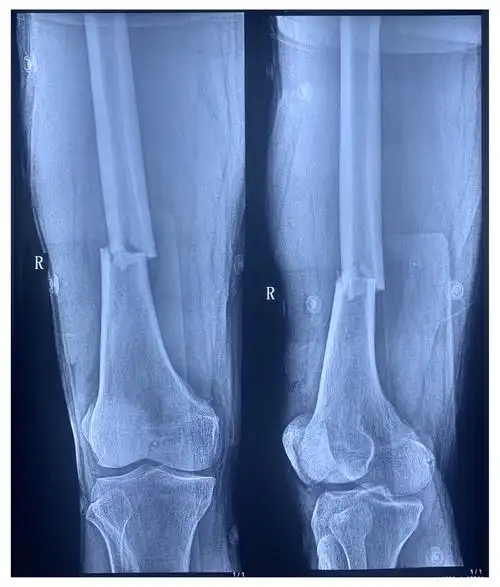

右侧x线,股骨远端横行骨折,ao分型:32a3c